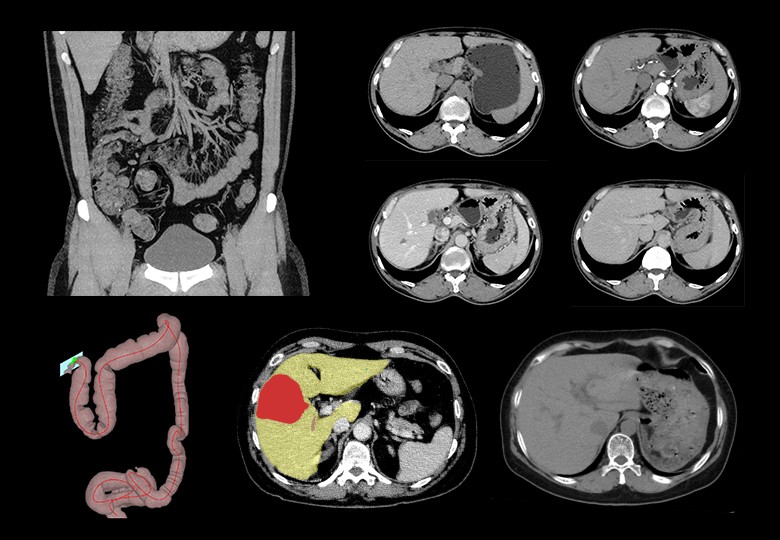

Abdomen Scan